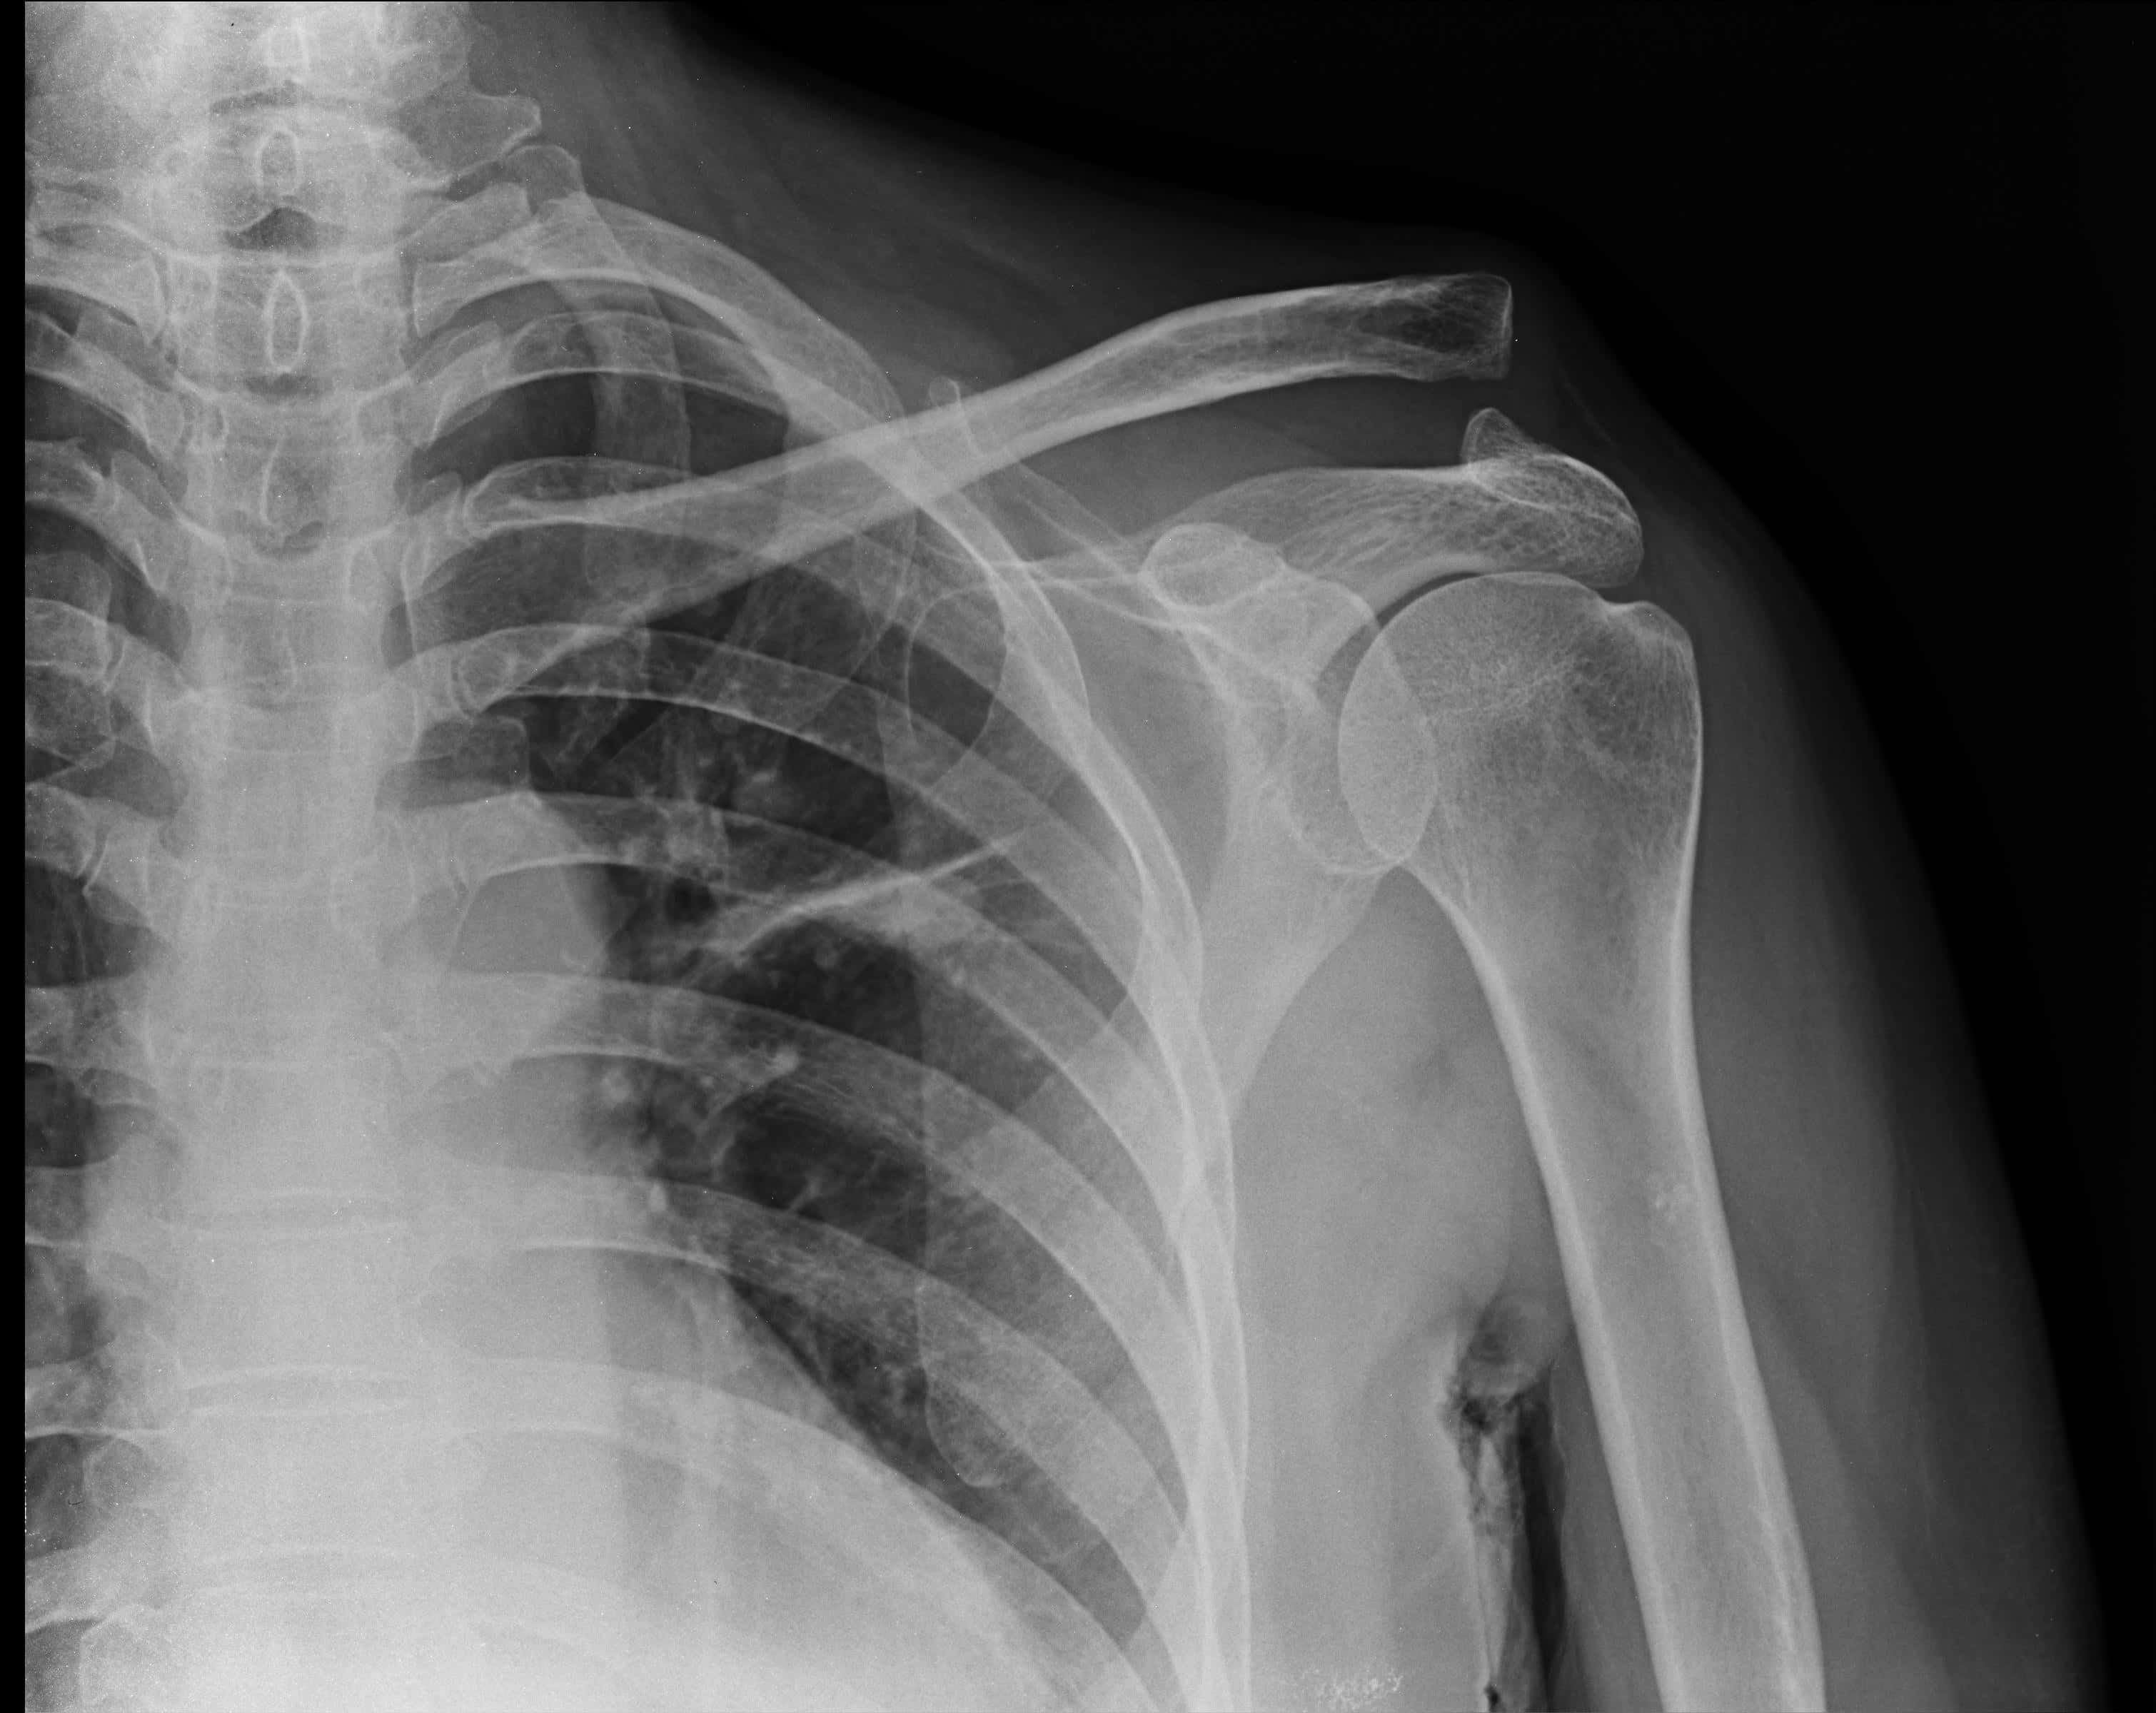

ပုခုံးနာကျင်ခြင်းဟာ ဖြစ်လေ့ဖြစ်ထရှိတဲ့ အခြေအနေတခု ဖြစ်ပြီး ပုခုံးမှာ ထိခိုက်ဒါဏ်ရာ ရခြင်း၊ဒါဏ်ဖြစ်ခြင်း ဒါမှမဟုတ် အခြားသော ပြဿနာတွေကြောင့် ဖြစ်ပေါ်လာနိုင်ပါတယ်။ ဒါပေမယ့် တခါတရံ ပုခုံးနာကျင်ခြင်းဟာ လည်ပင်းမှာဖြစ်ပေါ်နေတဲ့ ပြဿနာတခုခုကြောင့်လည်း ဖြစ်လာနိုင်ပါတယ်။

လည်ပင်းမှာရှိတဲ့ အာရုံကြောအဖိခံရပြီ၊ထိခိုက်ပြီဆိုရင် နာကျင်မှုက ပုခုံးအထိ ရောက်လာနိုင်ပြီး အားနည်းပျော့ခွေခြင်း၊ထုံကျဉ်ခြင်းတွေကတော့ လက်တလျှောက်လုံးမှာ ပျံ့နှံ့သွားနိုင်ပါတယ်။

ဒီလိုအခြေအနေကို ဆေးပညာဝေါဟာရနဲ့ “လည်ပင်းအာရုံကြောညပ်ခြင်း” လို့ ခေါ်ဝေါ်လေ့ရှိပြီး အောက်ဖော်ပြပါ ရောဂါလက္ခဏာတွေကို ခံစားရလေ့ရှိပါတယ်။

“လည်ပင်းအာရုံကြောညပ်ခြင်း” ဟာ ကျောရိုးထိခိုက်ဒါဏ်ရာရခြင်း ဒါမှမဟုတ် အသက်အရွယ် ကြီးရင့်လာခြင်းကြောင့် ဖြစ်နိုင်ပါတယ်။